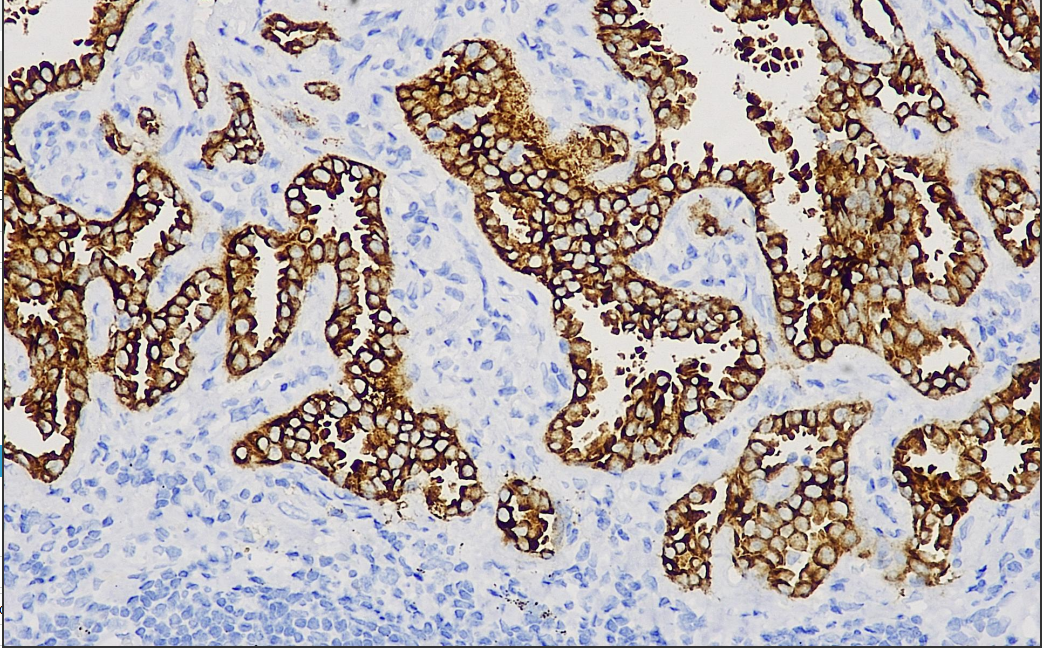

Positive control: mesenchymal large cell lymphoma/lung adenocarcinoma

Mesenchymal large cell lymphoma is characterized by CD30+, often accompanied by a t(2:5)(p23:q35) translocation, which results in the expression of an 80 kD complex protein, named NPM-ALK, which is recognized by the antibody to this alkali-mutated lymphoma kinase, ALK. Recent studies have shown that ALK-positive ALCL has a better prognosis than ALK-negative patients.

Alk/P80 Antibody Reagent binds specifically to the Alk/P80 molecular antigen. Immunohistochemistry kits containing Alk/P80 Antibody Reagent are suitable for precise diagnosis of interstitial large cell tumors, and can also be used for the study of ALK gene rearrangement in lung adenocarcinoma.